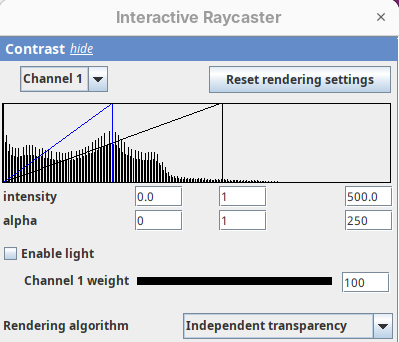

- Set the alpha

minto250.

This will make darker pixels more transparent and information gets lost.

- Set it to

0.

By default 3Dscript sets the gamma value of alpha to 2.0. That’s a good default for fluorescence microscopy (see the next dataset below), but since this is MRI data, we need to tweak it a little differently.

- Set the alpha gamma value to

1.0.

Note that this improves the visualization as the head’s surface becomes better visible.

- Now set the alpha

maxto250.

The surface will become even more solid because we are defining that pixels that have a value above 250 will be fully opaque.